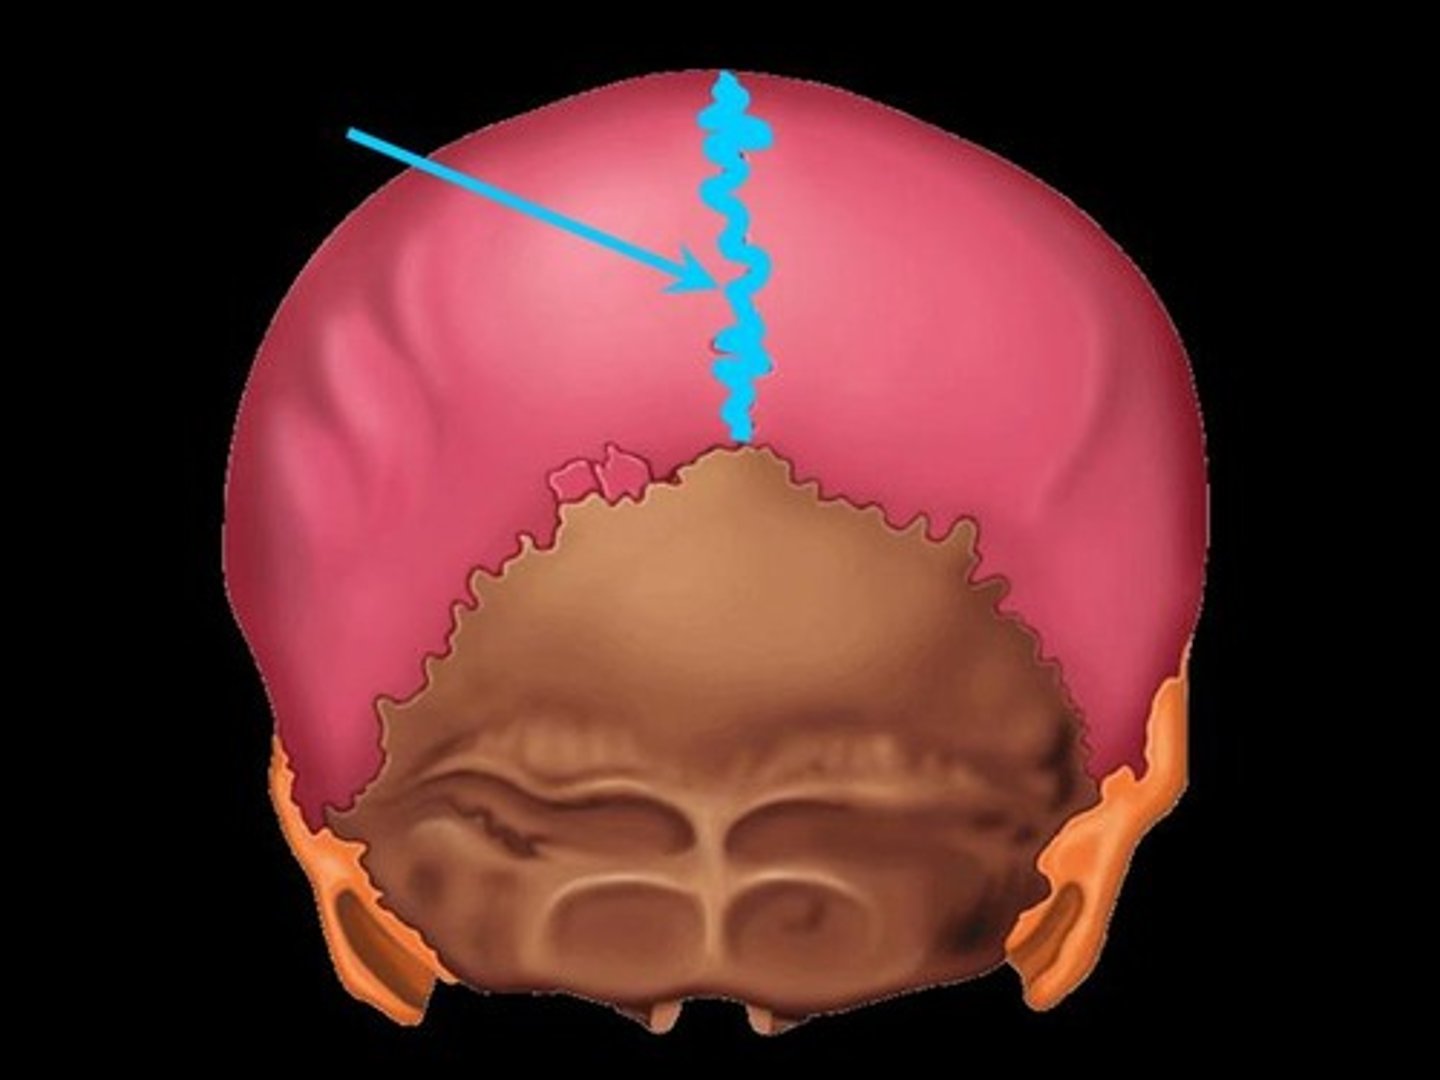

lambdoid suture

between parietal bones and occipital bone

lambda

junction of sagittal and lambdoidal sutures

Sagittal Craniosynostosis

premature closure of sagittal suture resulting in posterior elongation